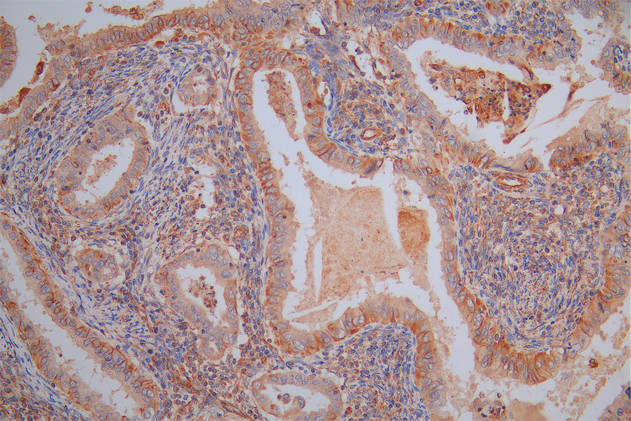

Immunohistochemistry of paraffin-embedded human liver cancer using CSB-PA022422LA01HU at dilution of 1:100